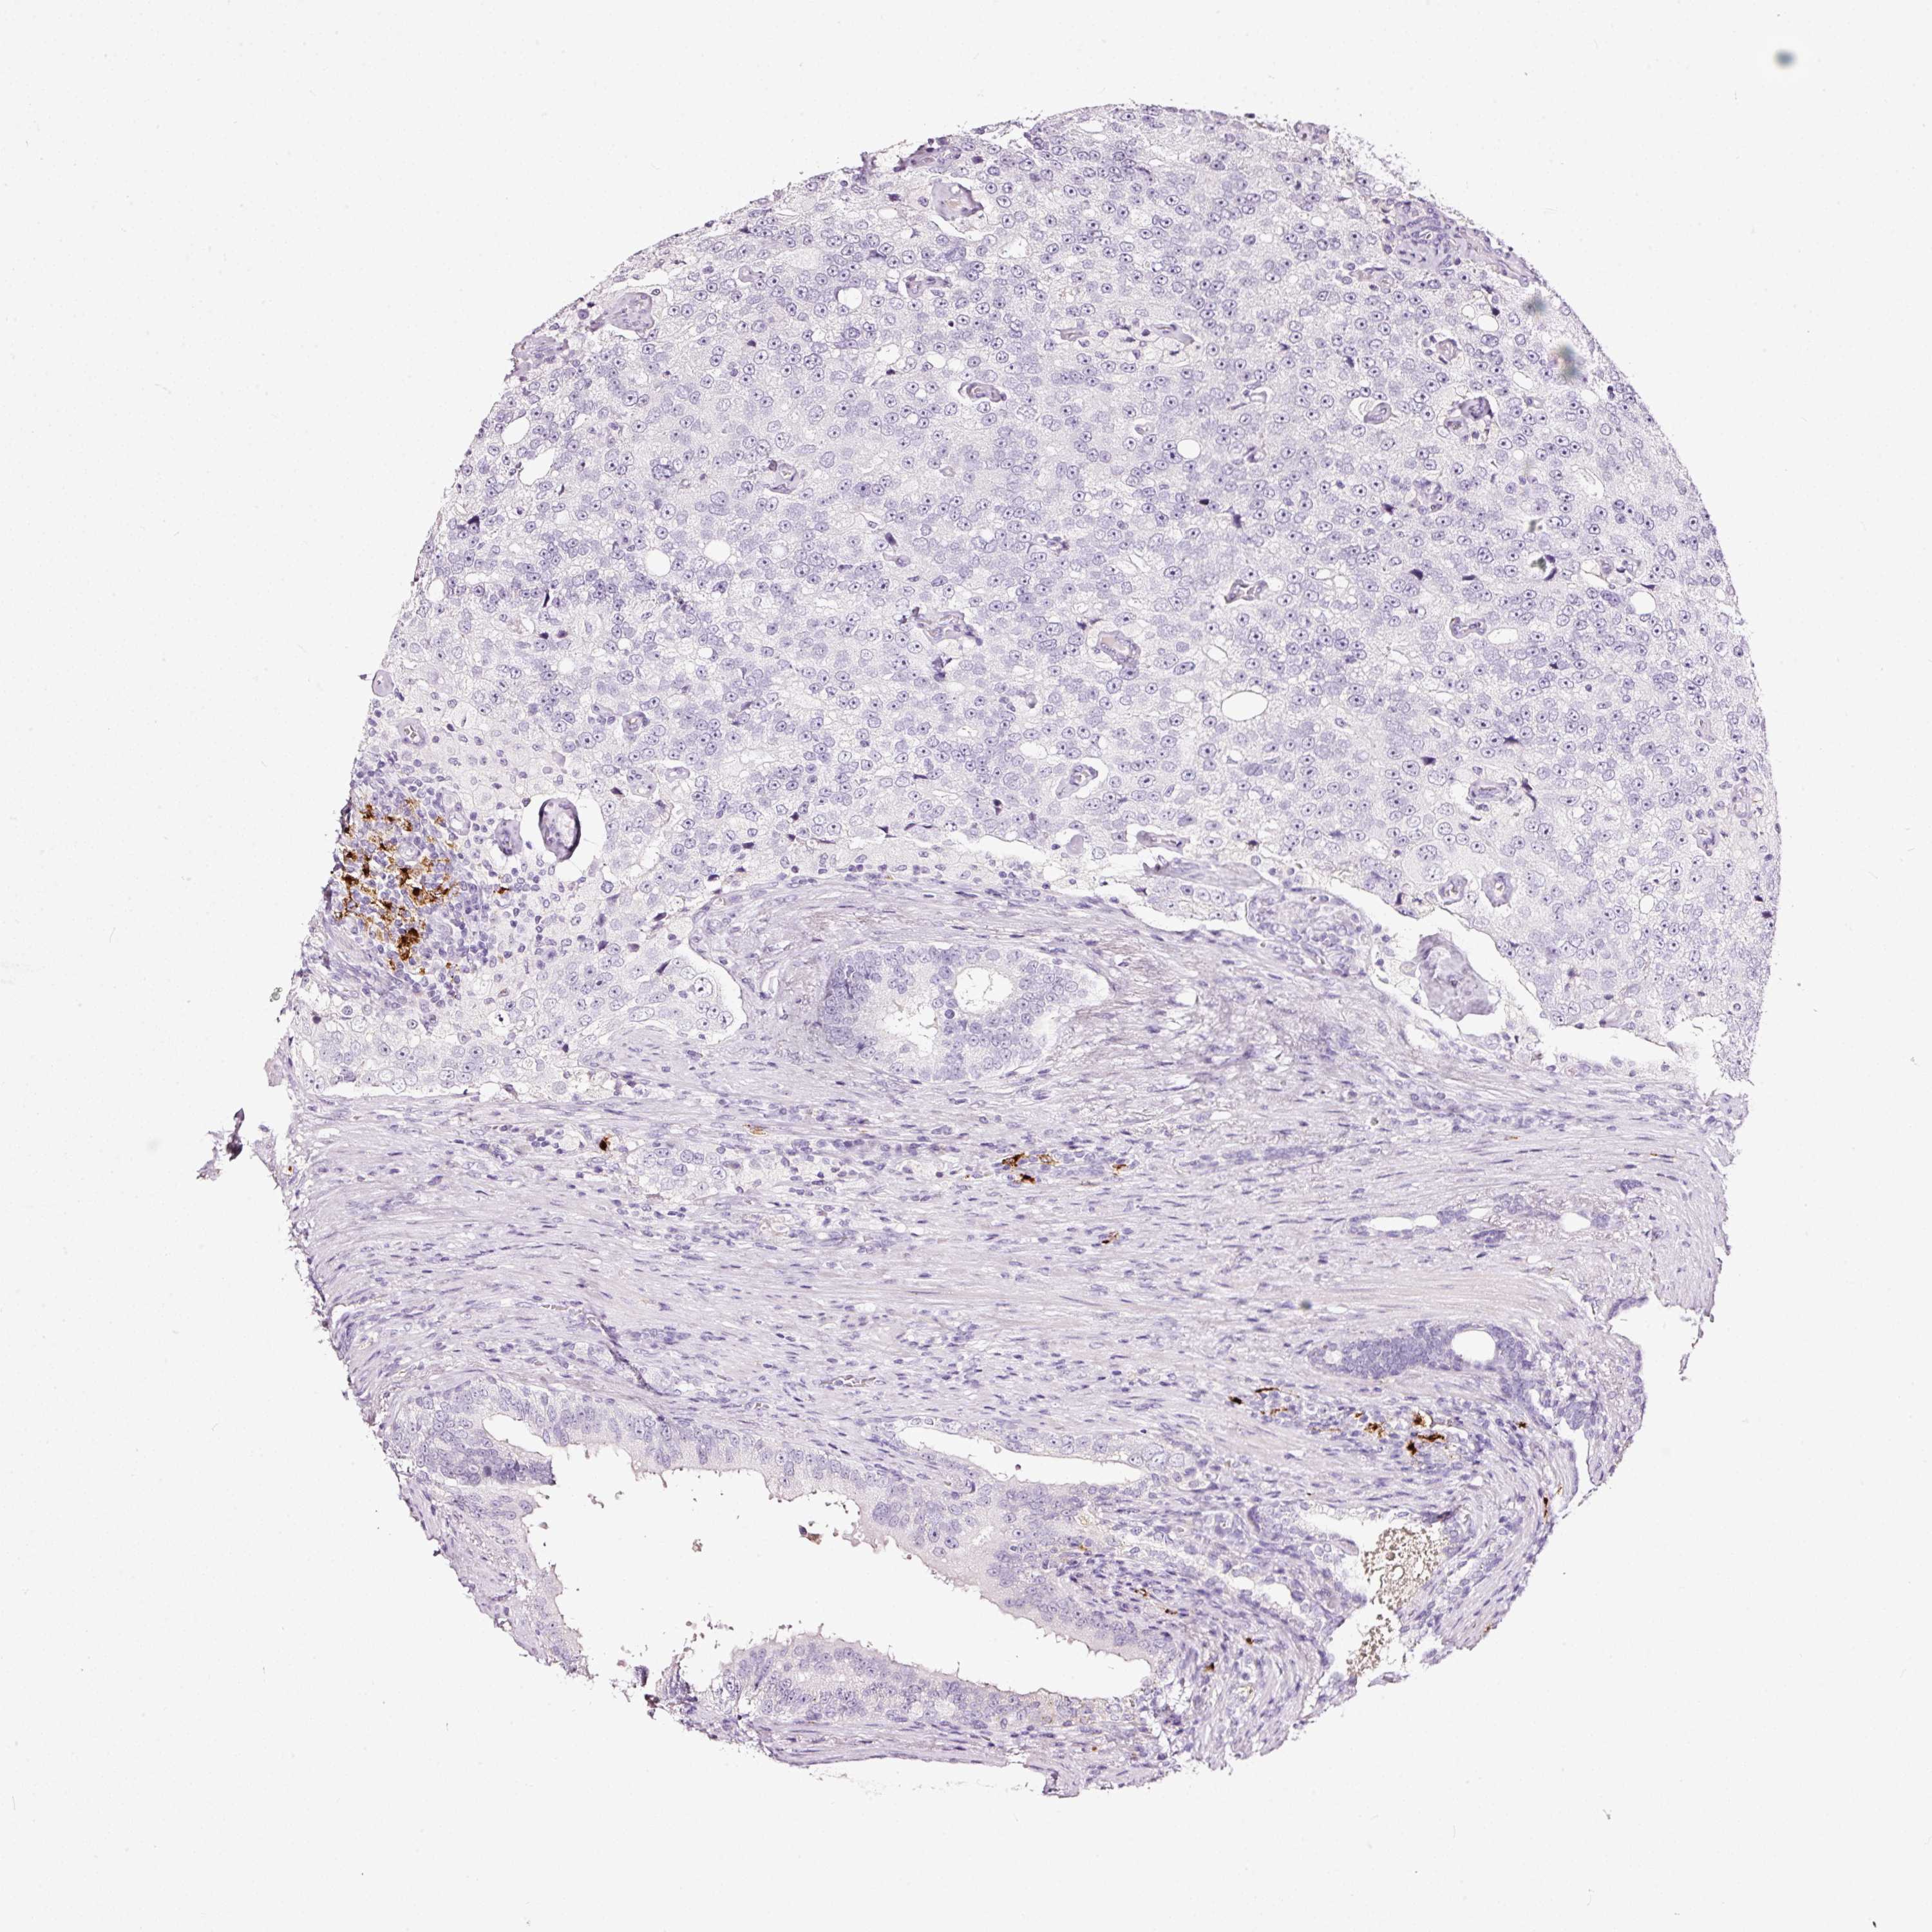

PROSTATE CANCER - Protein expressioni

A mouse-over function shows sample information and annotation data. Click on an image to view it in a full screen mode. Samples can be filtered based on level of antibody staining by selecting one or several of the following categories: high, medium, low and not detected. The assay and annotation is described here.

Antibody stainingi

Antibody staining in the annotated cell types in the current human tissue is reported as not detected, low, medium, or high, based on conventional immunohistochemistry profiling in selected tissues. This score is based on the combination of the staining intensity and fraction of stained cells.

Each image is clickable and will lead to virtual microscopy that enables deeper exploration of all samples and also displays staining intensity scores, fraction scores and subcellular localization as well as patient and tissue information for each sample.

Antibody HPA051467

Antibody CAB025133

Staining

High

Medium

Low

Not detected

Intensity

Strong

Moderate

Weak

Negative

Quantity

>75%

75%-25%

<25%

None

Location

Nuclear

Cytoplasmic/membranous

Cytoplasmic/membranous,nuclear

Adenocarcinoma, NOS

Adenocarcinoma, High grade

Adenocarcinoma, Low grade